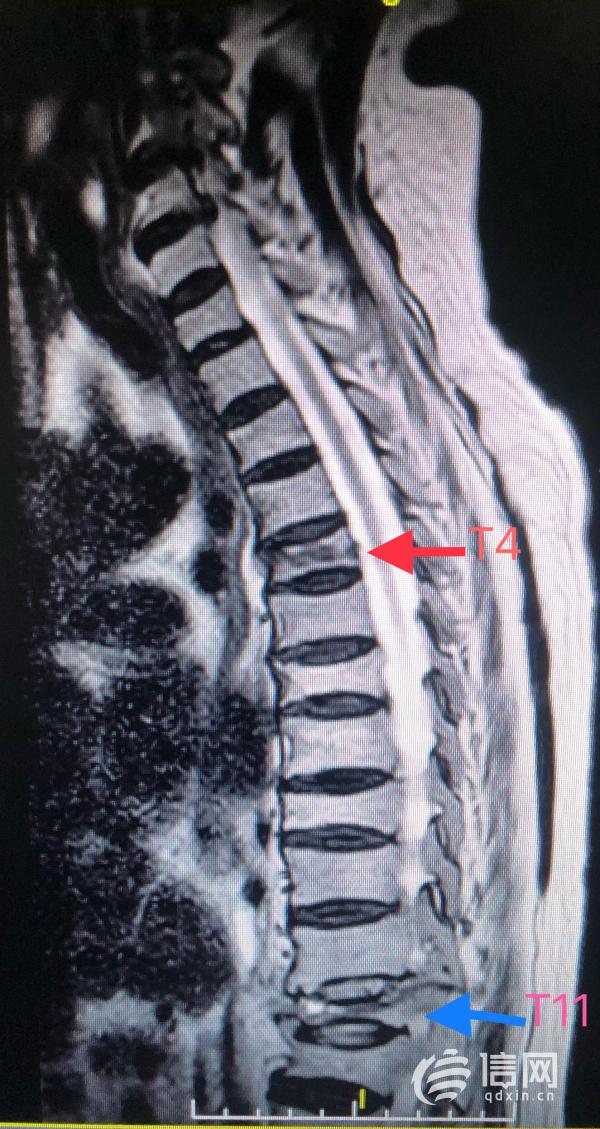

蔡女士入院後,經過平度市人民醫院骨二科專家、心內科專家、呼吸與重症醫學科專家、胸外科專家聯合會診後診斷為:胸椎骨折、胸部脊髓損傷、多發肋骨骨折、雙側胸腔積液、胸骨骨折等疾病。

潘雲春副主任醫師建議患者在病情穩定後手術治療,蔡女士及其家人剛開始因高齡老人基礎疾病較多,且聯合損傷存在,老人及家屬對於手術治療比較排斥。潘雲春副主任醫師帶領大家積極討論後決定對蔡女士採用經皮椎骨成形微創手術,儘量減少手術創傷及術後併發症的發生。再次與家人溝通後,得到了家人和蔡女士的理解和支援,局麻下為蔡女士實施了胸4椎體及胸11椎體微創經皮椎骨成形術,手術過程很順利,手術用時60分鐘,基本無出血,刀口3毫米。

據悉,平度市人民醫院已熟練掌握T5及以下椎體的微創手術(PVP或PKP),潘雲春副主任醫師表示蔡女士的T4椎體壓縮性骨折在術前評估時就面臨著嚴峻的挑戰,對T4椎體在C臂透視下實施微創手術在平度市人民醫院尚屬首例,且T4椎體壓縮骨折合併胸骨體骨折有出現遲發性神經功能障礙的可能,無形中增加了手術的難度,對手術醫師精準的定位,穿刺的力度的大小及角度提出了更高的要求。

骨二科潘雲春副主任醫師表示,胸腰椎骨質疏鬆性骨折是引起老年人胸背部及腰痛的一個重要原因,對於沒有明顯壓縮的椎體骨折,如不進行MR檢查,往往造成漏診。微創經皮椎骨成形術是近年一種新型微創手術,該手術具有創傷小、安全性高、療效確切及術後恢復快的優點。許多老人已透過此項技術減去了痛苦,門診複查時效果比較滿意。因此,高齡老人骨折應立即到醫院就診,千萬不要放棄治療。